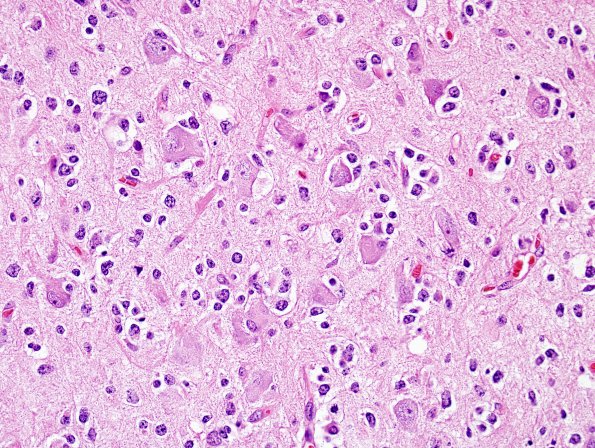

Washington University Experience | NEOPLASMS (GLIAL) | Oligodendroglioma - IDH1 mutant, del 1p19q - Grade 3 | 13A4 Oligodendroglioma, Gr3 (Case 13) H&E 10

There is a significant involvement of the cortex with prominent satellitosis. (H&E)